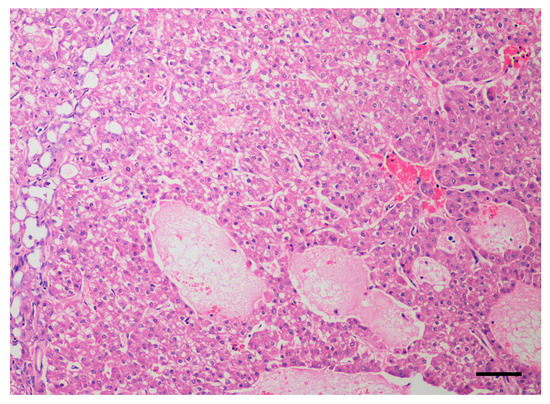

2.1. Dogs and Tumor Characteristics